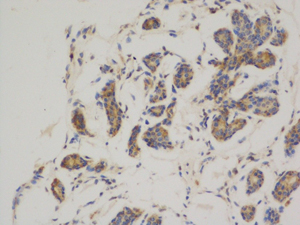

Mouse Monoclonal ABCB5 Antibody

中文名:ABCB5抗体

Catalog:IPDX20760

Size: 50μl / 100μl

Application: WB IF IHC ICC FCM Elisa

Reactivity:Human,Mouse,Rat

Synonyms:ABCB5 P-gp; ATP binding cassette sub family B (MDR/TAP) member 5; P glycoprotein ABCB5

Type:Primary antibody